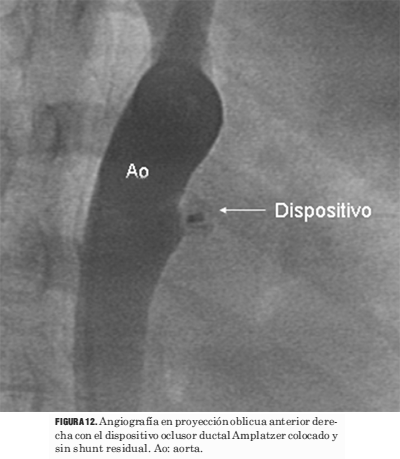

Los procedimientos de cierre del ductus se llevaron a cabo sin el uso simultáneo del ecocardiograma (figuras 9, 10, 11, 12 y 13).

Figura 12. Angiografía en proyección oblicua anterior derecha con el dispositivo oclusor ductal Amplatzer colocado y sin shunt residual. Ao: aorta.